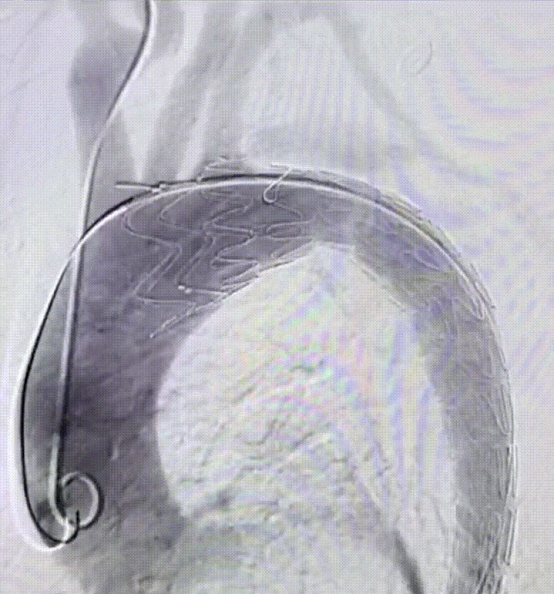

成功释放主体支架

成功置入分支支架,造影显示支架塑形良好,无内漏,LSA血流通畅